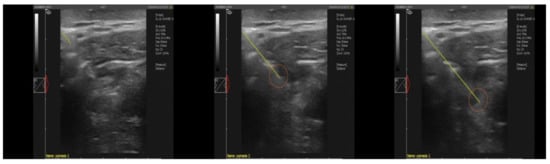

2.1. Material Collection